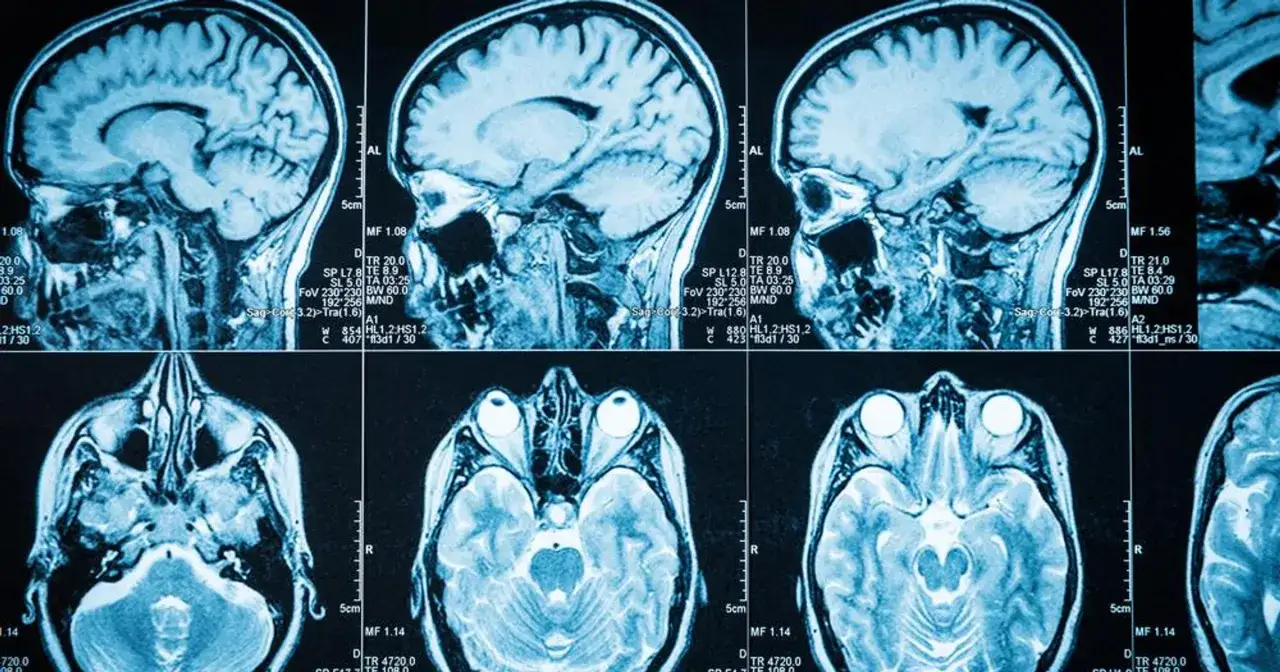

Guz mózgu to poważne schorzenie, które może prowadzić do różnorodnych objawów psychicznych. Objawy te często są pierwszymi sygnałami choroby, które mogą być mylone z codziennym stresem lub zmęczeniem. Warto zrozumieć, jak lokalizacja guza w mózgu wpływa na zachowanie i samopoczucie pacjenta. Wiele osób nie zdaje sobie sprawy, że zmiany w osobowości, problemy z pamięcią czy zaburzenia nastroju mogą być związane z obecnością guza. Dlatego tak ważne jest, aby być świadomym tych symptomów i reagować na nie odpowiednio wcześnie.

Guz mózgu może prowadzić do różnorodnych objawów psychicznych, które często są pierwszymi sygnałami choroby. Wiele osób nie zdaje sobie sprawy, że zmiany w zachowaniu mogą być związane z obecnością guza. Wczesne rozpoznanie tych symptomów jest kluczowe, ponieważ może prowadzić do szybszej diagnozy i leczenia. Warto zwrócić uwagę na to, jak lokalizacja guza w mózgu wpływa na psychikę pacjenta oraz jakie zmiany mogą wystąpić.Objawy psychiczne mogą być subtelne i często są mylone z normalnym stresem lub zmęczeniem. Dlatego tak ważne jest, aby być czujnym na wszelkie zmiany w osobowości, zachowaniu czy nastroju. W przypadku wystąpienia poważnych zaburzeń u osoby, która wcześniej nie miała takich problemów, należy rozważyć konsultację z lekarzem. Wczesne wykrycie problemu psychicznego może znacznie poprawić jakość życia pacjenta oraz jego bliskich.